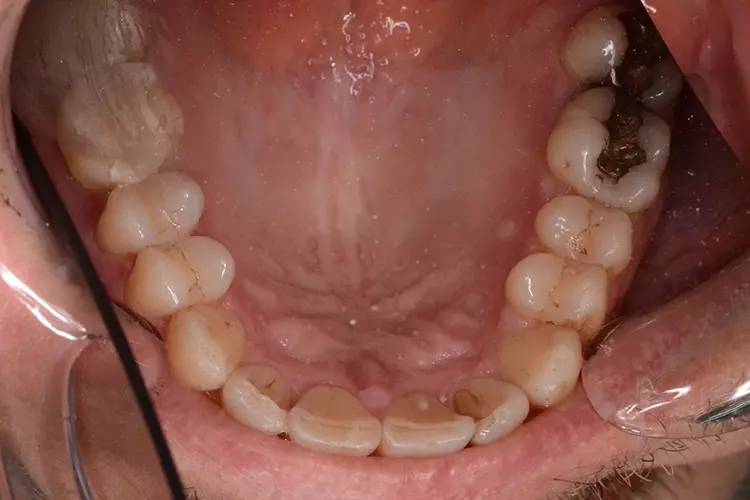

Bei dem heute 49-jährigen Patienten wurde seit Kindertagen versäumt, die Ober- und Unterkieferzahnbögen kieferorthopädisch auszurichten. Der Patient leidet seitdem stark unter seinen Zahnfehlstellungen.

Die Fraktur des stark elongierten Zahnes 21 war für den Patienten der Ausgangspunkt, sowohl die Front des Ober- als auch des Unterkiefers prothetisch überarbeiten zu lassen. Dabei wurde der frakturierte Zahn 21 durch ein navigiert eingesetztes Sofortimplantat ersetzt, während die verschachtelt stehenden Zähne 12 und 42 durch eine Brückenversorgung korrigiert wurden (Abb. 4a-j).